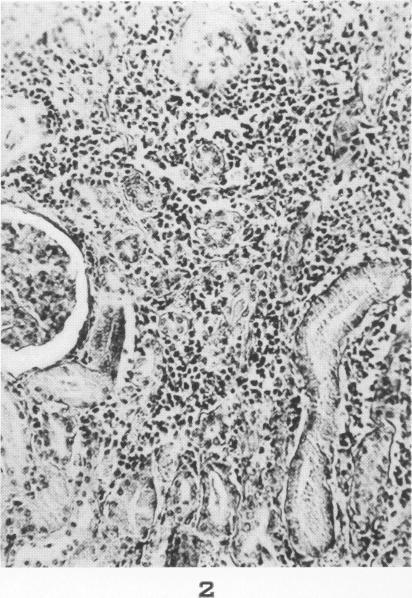

Lesions of skeletal muscle in leptospirosis; review of reports and an experimental study.

Am J Pathol. 1955 May-Jun;31(3):501-19.